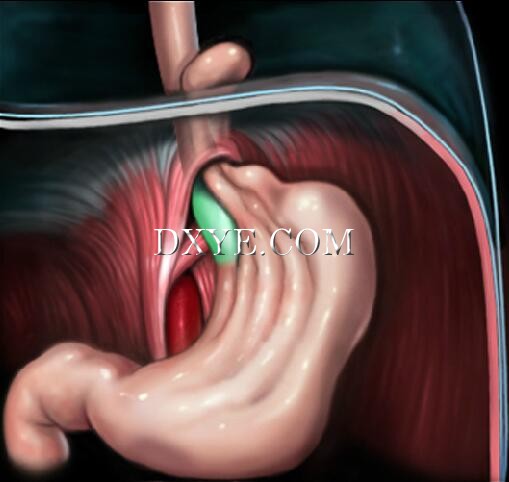

• Type II hiatal hernias

Type II, or paraesophageal hiatal hernias, occur through a defect in the phrenoesophageal ligament.

The gastroesophageal junction nonetheless remains in the abdominal cavity. |